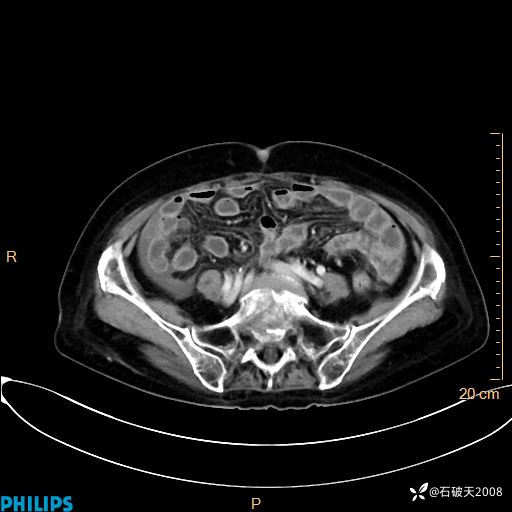

MIP